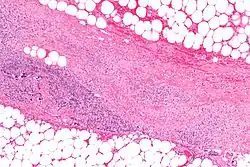

.webp.png)

Necrotizing fasciitis is ideally a clinical diagnosis based on symptoms. Due to the need for rapid surgical treatment, the time delay in performing imaging is a major concern.[15] Hence, imaging may not be needed if signs of a necrotizing infection are clear. However, due to the vague symptoms associated with the earlier stages of this disease, imaging is often useful in clarifying or confirming the diagnosis.[15]

Both CT scan and MRI are used to diagnose NF, but neither are sensitive enough to rule out necrotizing changes completely.[2]